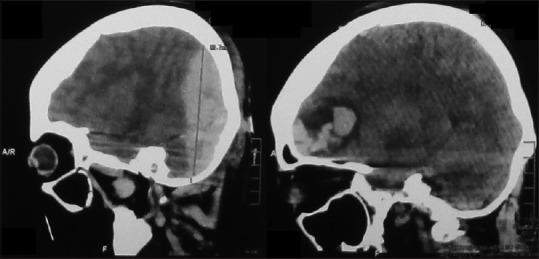

Traumatic supra- and infra-tentorial extradural hematoma (TSIEDH) is a rare lesion constituting <2% of all extradural hematomas. There are only a few published articles about TSIEDH. This study included three patients with TSIEDH who were treated and operated at Dr. Soetomo General Hospital, Surabaya, Indonesia, from August 2015 to July 2016. Two patients sustained injuries in traffic accidents and one patient was injured by fall. The male to female ratio was 1:2. Glasgow Coma Scale (GCS) score ≤8 was present in one and GCS score of 9-12 was present in two patients. The brain computed tomography scan verified linear fracture of occipital bone in one and linear fracture of occipital bone with lambdoid suture separation in two patients. Early diagnosis and early surgical intervention of TSIEDH are imperative because the deterioration of TSIEDH is sudden and quick. We presented our experience in treating patients with TSIEDH in Dr. Soetomo General Hospital, Surabaya, Indonesia.

创伤性幕上和幕下硬膜外血肿(TSIEDH)是一种罕见的病变,占所有硬膜外血肿的比例不到2%。关于TSIEDH的已发表文章很少。本研究纳入了2015年8月至2016年7月在印度尼西亚泗水苏托莫综合医院接受治疗和手术的3例TSIEDH患者。2例患者在交通事故中受伤,1例患者因跌倒受伤。男女比例为1:2。1例患者格拉斯哥昏迷量表(GCS)评分≤8,2例患者GCS评分为9 - 12。脑部计算机断层扫描显示1例患者枕骨线性骨折,2例患者枕骨线性骨折伴人字缝分离。由于TSIEDH的恶化突然且迅速,因此对其进行早期诊断和早期手术干预至关重要。我们介绍了在印度尼西亚泗水苏托莫综合医院治疗TSIEDH患者的经验。